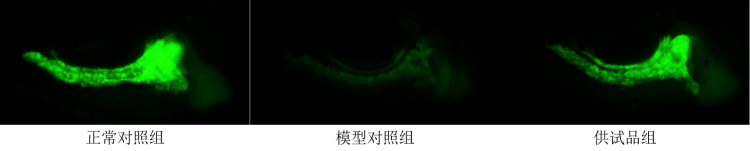

图3. 斑马鱼胰腺细胞荧光强度典型图

图4. 斑马鱼胰腺细胞荧光强度柱形图

从实验结果可以看到,服用供试品胰腺中性粒细胞数量比模型对照组明显降低,且胰腺细胞荧光强度比模型对照组明显升高。

1.经过每组30尾斑马鱼的对比实验,相对于模型对照组,服用或者注射供试品组之后,胰腺中性粒细胞数量降低、胰腺细胞荧光强度升高。